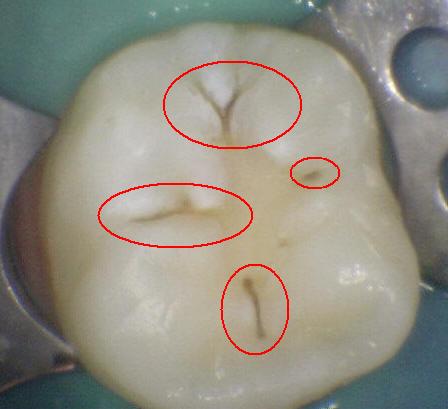

Código 1(Caries

Inicial): Primer cambio

visible en el esmalte seco

- Cuando se observa la

superficie húmeda no hay evidencia de cambio de color

que se pueda atribuir a actividad cariogénica, pero

después del secado prolongado con aire (durante

aproximadamente 5 segundos) se observa una opacidad o

pigmentación compatible con desmineralización que no es

consistente con el esmalte clínicamente sano.

- (Mancha blanca

/ marrón)